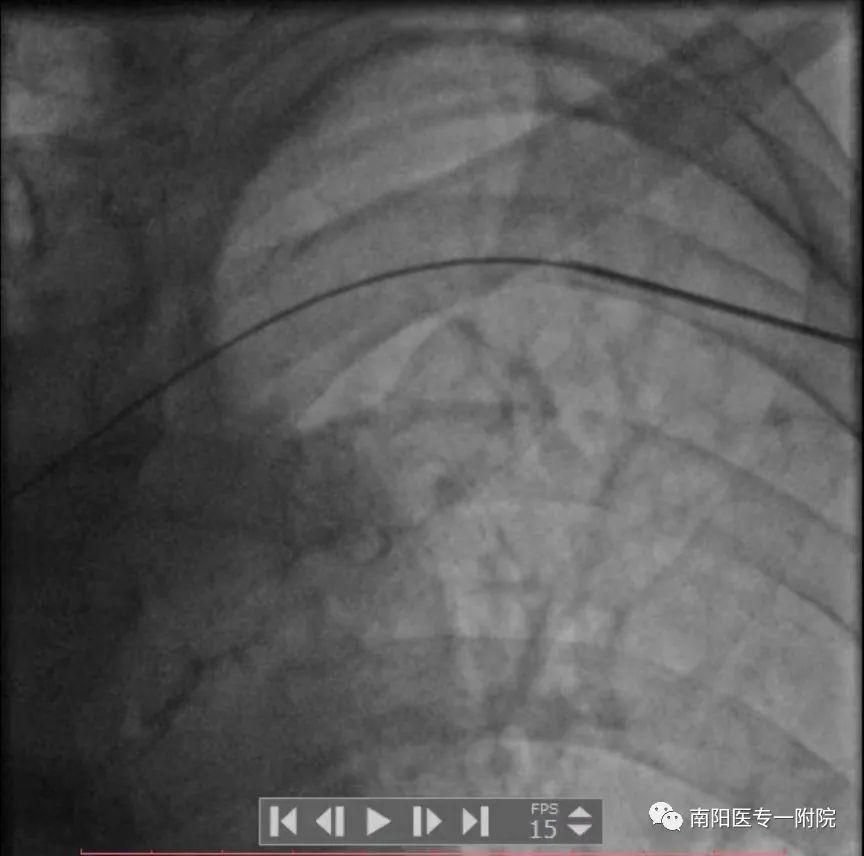

3月17日下午南阳医专一附院心内三团队为86岁高龄反复室速老爷子顺利完成埋藏式心脏除颤装置ICD植入,入院后经冠脉造影明确冠脉情况后,排除冠脉因素,经腋静脉穿刺植入除颤电极,分离胸大肌,除颤装置植入深部肌肉层,采用无创缝合切口!